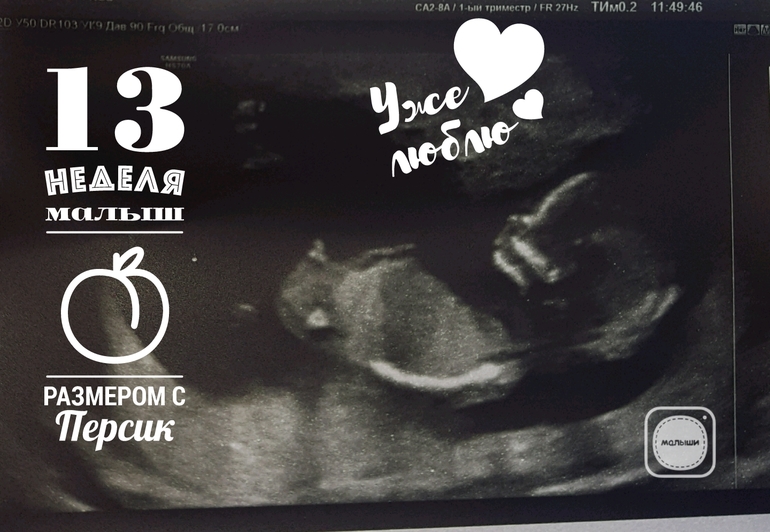

нам с таким бугорком сказали что девочка☺ очень похоже)))

у нас вот так торчало)

а вот лобик на мальчика))